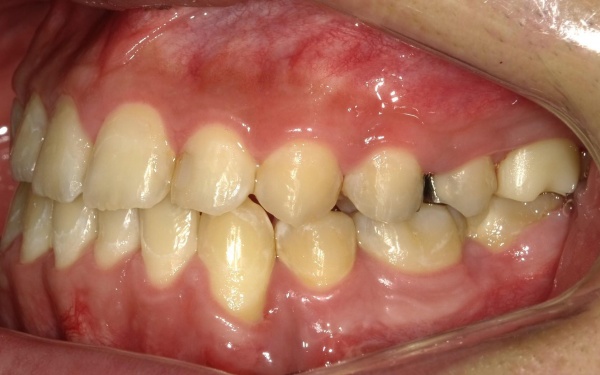

10代男性 顎変形症が原因で下顎がずれて非対称になっていた噛み合わせをサージェリーファースト法を併用した矯正治療で改善した症例

ご相談内容 「顔と顎がゆがんでいて、見た目が悪くしゃべりにくいのが気になる。また、前歯が噛み合っていないため、食べ物を噛み切ることができない」とご相談いただきました。

カウンセリング・診断結果 拝見したところ、骨格の問題により下前歯が上前歯より前に出ている前歯部反対咬合と、前歯が開いて噛み合わないオープンバイトが認められました。

さらに、下顎の骨が右方向にずれて上下の歯が噛み合う面が斜めになっていることで、顔面の非対称も見られます。

これらは顎変形症と呼ばれる状態で、現在は食べ物をしっかりと噛む機能が大きく制限されているうえ、発音や見た目に悪影響が出ていました。

治療前

治療前画像 治療前画像 治療前画像 治療前画像 治療前画像 治療前画像